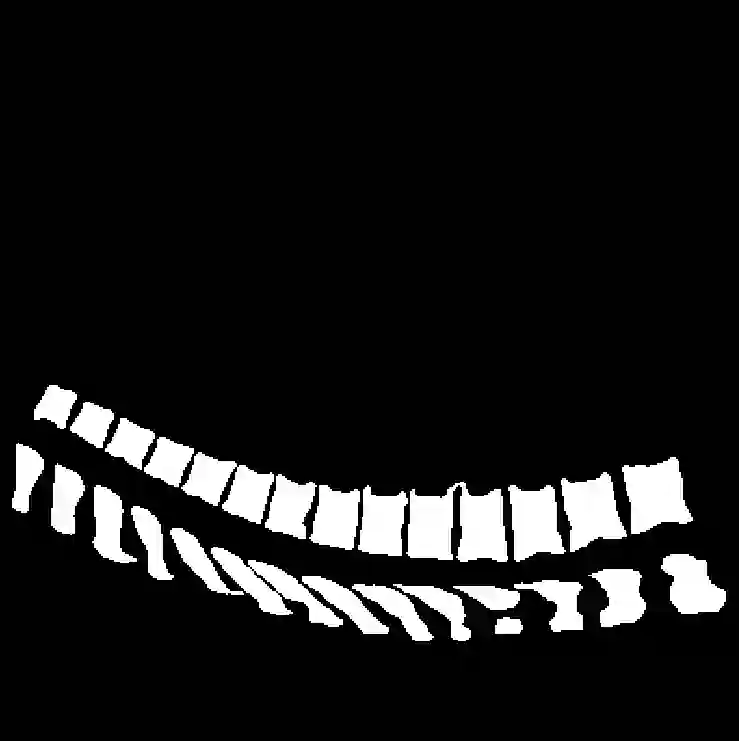

Vertebrae localization, segmentation and identification in CT images is key to numerous clinical applications. While deep learning strategies have brought to this field significant improvements over recent years, transitional and pathological vertebrae are still plaguing most existing approaches as a consequence of their poor representation in training datasets. Alternatively, proposed non-learning based methods take benefit of prior knowledge to handle such particular cases. In this work we propose to combine both strategies. To this purpose we introduce an iterative cycle in which individual vertebrae are recursively localized, segmented and identified using deep-networks, while anatomic consistency is enforced using statistical priors. In this strategy, the transitional vertebrae identification is handled by encoding their configurations in a graphical model that aggregates local deep-network predictions into an anatomically consistent final result. Our approach achieves state-of-the-art results on the VerSe20 challenge benchmark, and outperforms all methods on transitional vertebrae as well as the generalization to the VerSe19 challenge benchmark. Furthermore, our method can detect and report inconsistent spine regions that do not satisfy the anatomic consistency priors. Our code and model are openly available for research purposes.